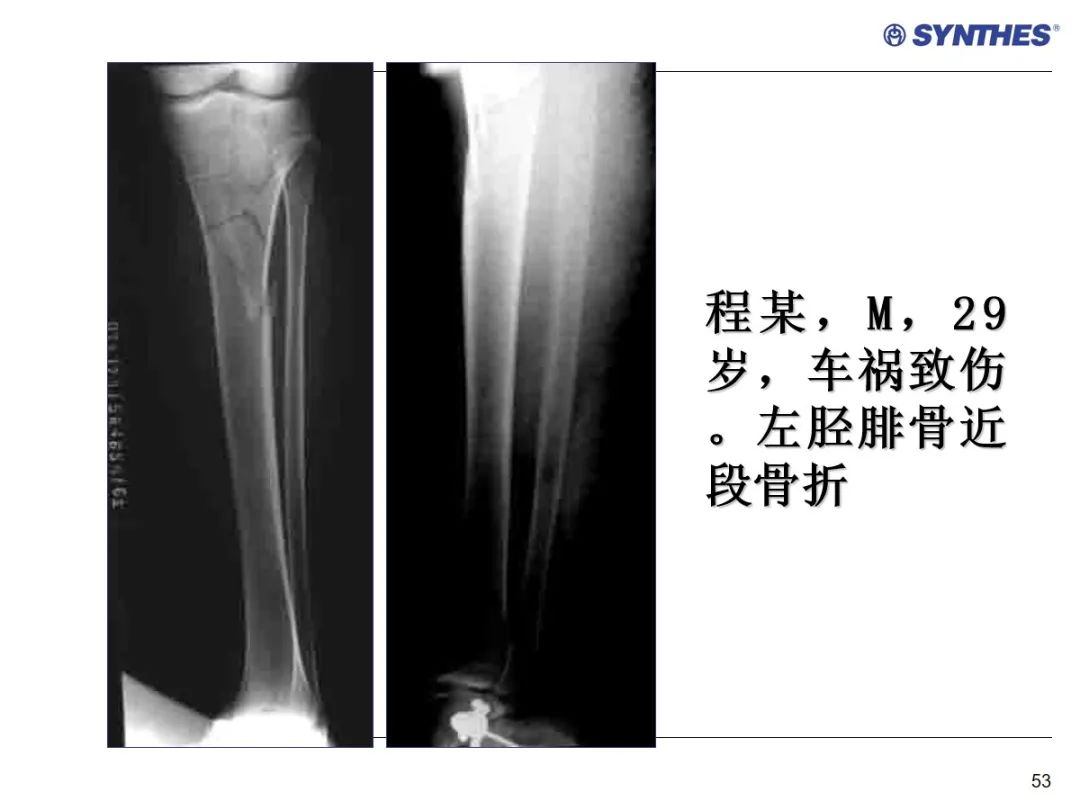

LISS微创固定系统应用技巧,原来如此简单!